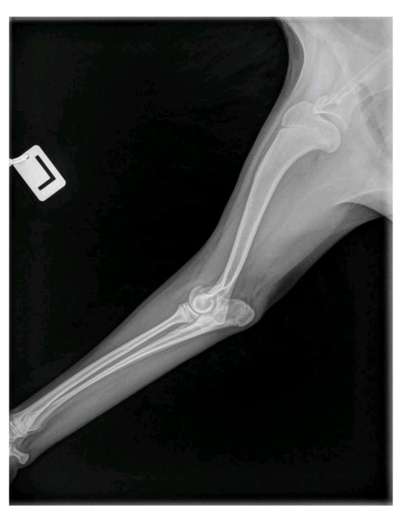

Hallo liebe Leute, Aufgrund mehrwöchiger Lahmheit vorne links bei unserem 6 Monatigen Hund (Japanspitz, eher kleine - mittelgroße Rasse) haben wir in einer Tierklinik ihn röntgen lassen und anschließend ins CT gegeben. Nun hat er laut Ärzten im Ellenbogen eine beidseitige OCD und soll zumindest auf der linken Seite operiert werden. Wir sind recht überfordert mit der Diagnose und wollen eine 2. Meinung noch einholen. Angehängt sind die Bilder. Unser Hund hatte keine Unfälle (natürlich ist er mal im Laufen auf glatten Boden daheim mal weggerutscht). Gassi sind wir immer nach der 5-10 Minutenregel pro Monat gegangen. Treppen wurde und wird er getragen. Kein wildes Spiel mit anderen Hunden. Er darf nicht allein auf die Couch. Essen bekam er Anfangs das HappyDog für Welpen, ab und zu bisschen Naturjoghurt und Buttermilch. Seit einer ganzen Weile erhält er aber nun das Welpenfutter mit Lamm von Tails and Tales. Das frisst er ohne Joghurt (das vorherige TroFu wollte er kaum noch essen, daher der Wechsel). Leckerlis bestehen, wenn, aus seinem Trockenfutter, weil er das sehr gern mag. Oder getrocknetes Lamm oder Pferd. Weil er vor einer Weile Giardien hatte bekommt er noch was zum Aufbau der gesunden Darmflora und hat inzwischen wieder guten Stuhlgang etc. Das Lahmen schwankt übrigens. Jetzt läuft er seit 2 Tagen recht gut ( Gassi ist schon seit Wochen nur an der Leine), aber das muss nichts heißen. In seiner Zuchtstätte gab es seit 20 Jahren nicht so einen Fall und ich glaube das auch. Sind hier Experten für OCD? Was habt ihr für Erfahrungen? Was sagt ihr zu unserem Befund? Macht eine OP Sinn in diesem Fall? LG Anna

Upps, das Röntgenbild ist krass!

So wie das Bild aussieht muss operiert werden und das relativ schnell.